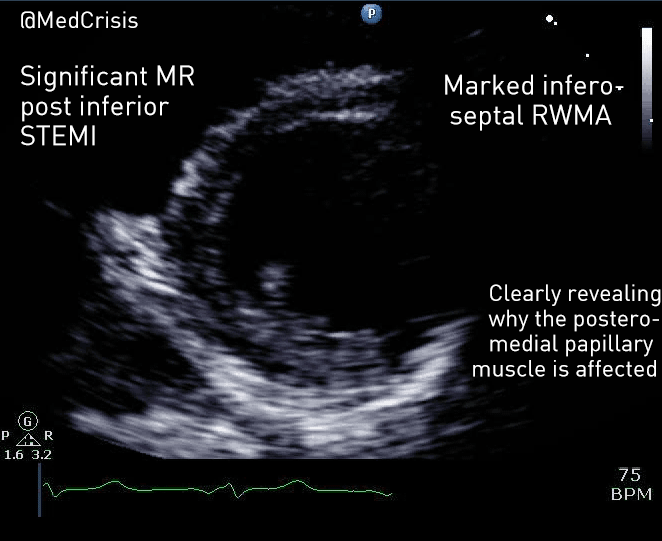

This parasternal short axis view gives the clearest demonstration of the problem. A regional wall motion abnormality is clearly seen affected the infero-septum and inferior wall. The rest of the left ventricle is contracting well.

The anterolateral papillary muscle is connected to the anterior mitral valve leaflet and receives a blood supply from both the left anterior descending artery (via a diagonal) and the circumflex artery (via an obtuse marginal). However the posteromedial papillary muscle only has one blood supply, which is the posterior descending artery, a branch of the right coronary artery in 90% of people.

Therefore one can appreciate why mitral valve problems are more common following an inferior STEMI. In this case an almost akinetic segment, which included the posteromedial papillary muscle, caused the posterior mitral valve leaflet to become fixed, causing mitral regurgitation. Even though overall left ventricular function was only mildly impaired on the echocardiogram, the regurgitant pressure into the lungs can precipitate pulmonary oedema.